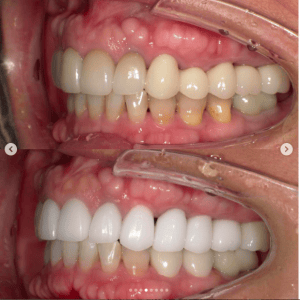

審美歯科症例集(ビフォーアフター)

より多くの症例をこちらのページでご紹介しておりますので、合わせてご覧ください

Case031

前歯が虫歯なのと、保険のプラスチックで大きく治療されていて色が悪いこと、歯並びが出っ歯気味であることを気にしてセラミックにしたいという主訴で来院された患者様です。

虫歯が大きかったところは神経治療をきちんと行い、

初診時を含めてトータル4回のご来院で完了です。

今回は前歯を下げる、歯列を整える、白すぎず自然に綺麗に見える色というご希望に沿って治療しました。

ご興味のある方はいつでもご相談ください。

担当 理事長 佐藤 悠野